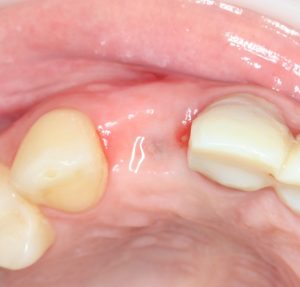

Кстати, обрати внимание на ширину альвеолярного гребня (левая картинка). Она чуть меньше 3 мм. Это объясняет, почему я засомневался в возможности установки имплантатов одновременно с остеопластикой. Понятно и без КЛКТ.

Возвращаемся к основной операционной области. Еще раз посмотрим на альвеолярный гребень, поофигеваем от его ширины и моих грандиозных планов: